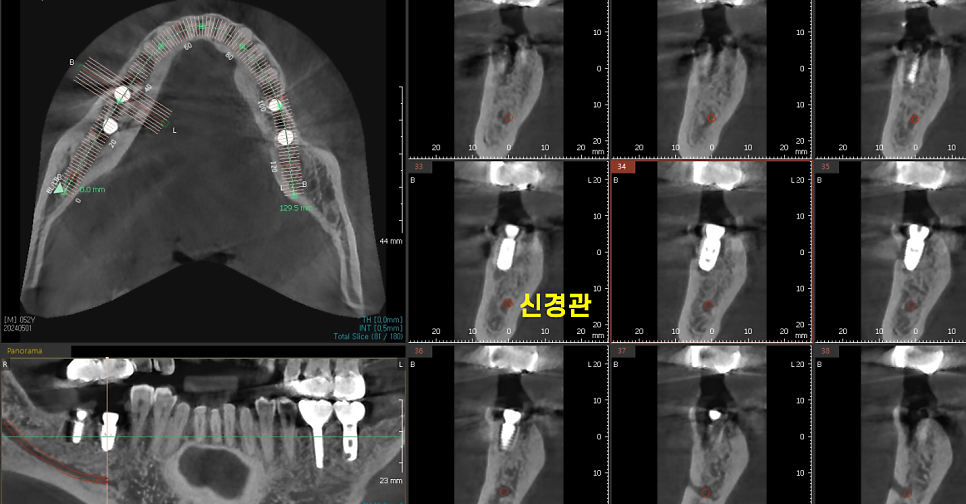

240501

빨간색 동그라미가 신경관인데

ct를 통해 1차 분석

2차로 네비게이션 임플란트 기술 활용

신경관을 피해 안전하게 임플란트 수술 완료하였습니다.